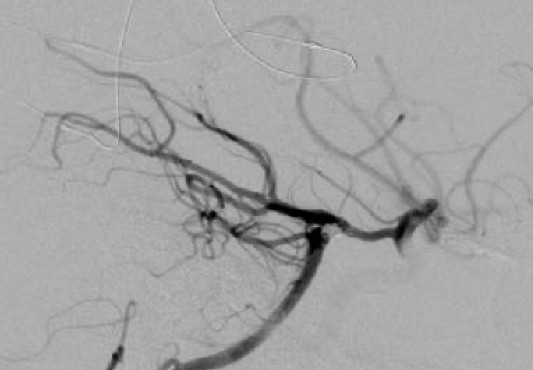

最终脑血管造影示所有分支血流通畅,动脉瘤无显影。